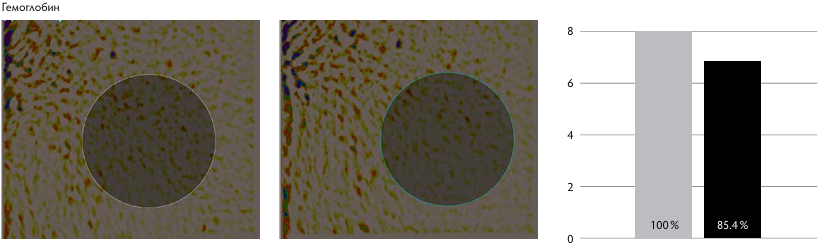

Рис. 1. Показатели пациентов I группы.

Рис. 1. Показатели пациентов II группы.

По данным Miravex Antera, в I группе отмечалось уменьшение содержания гемоглобина в среднем на 52–65 %, что говорит о снижении насыщения кожи поверхностными сосудами. Это свидетельствует в пользу эффективности методики при лечении пациентов с постакне, гиперпиг ментацией, поствоспалительными пятнами.

У пациентов II группы, по данным Miravex Antera, уменьшение содержания гемоглобина отмечалась в среднем на 15–21 %, меланина — на 1–5 %, улучшение текстуры кожи — на 18–25 %, снижение глубины морщин на 15–27 %, что сопоставимо с результатами пациентов I группы. По данным GAIS, у пациентов I группы отмечается удовлетворённость результатами процедуры на три балла, со стороны врача — тоже на три балла. У пациентов II группы пациенты расценивают результат на 2,4 балла, врач — на 2,4 балла.